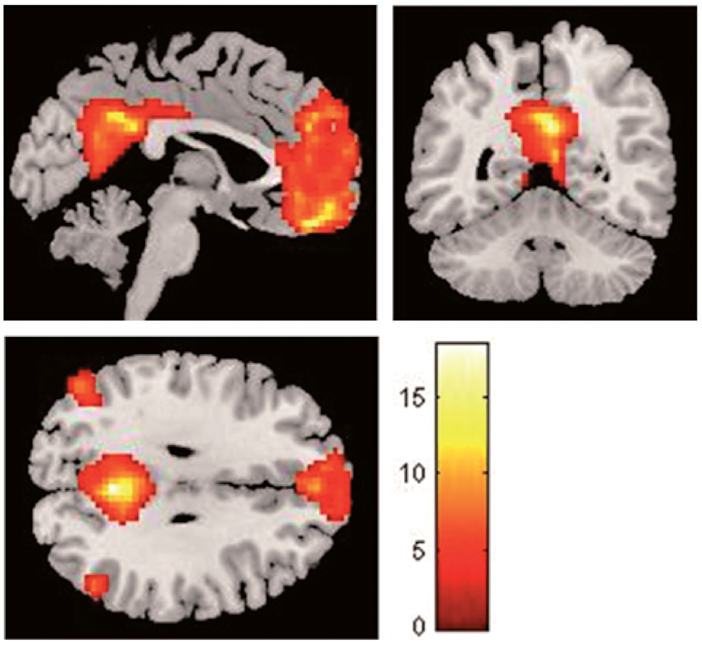

DMN results. The independent components extracted from each subject were used to perform group-level analysis (a one- sampled t-test with a threshold set at p < .05, Monte Carlo- corrected, as shown in Figure 1). Based on an ICA of resting-state fMRI data from all subjects, increased activation was found in the medial prefrontal area, precuneus, and bilateral parietal cortex. The coordinates and Z scores for the DMN areas are described in Table 2.

When age, sex, and the alternate IRI subscale were entered the model as covariates, cognitive subscale scores (i.e., IRI-PT scores) were positively correlated with activation of the superior medial frontal cortex bilaterally (x = -3, y = 42, z = 21, T = 10.01, IC = 0.16-0.22). In other words, cognitive scores were associated with functional connectivity in the superior medial frontal cortex in both hemispheres. Interestingly, emotional subscale scores (i.e., IRI-EC scores) were inversely correlated with the same brain region (right: x = 12, y = 60, z = 9, T = 6.17, IC = 0.17-0.29; left: x = -18, y = 51, z = 27, T = 12.81, IC = 0.15-0.20). Overall, higher scores in the emotional subscale were associated with low levels of connectivity in the bilateral superior medial frontal cortex (see Table 3 and Figure 2).